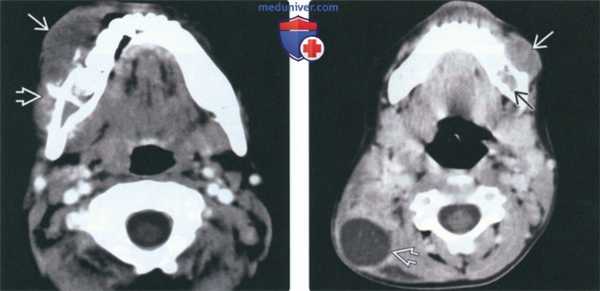

(Слева) На аксиальной КТ с КУ в нижней челюсти справа определяется большая опухоль, распространяющаяся в прилежащие мягкие ткани. Имеет место лучистая периостальная реакция со стороны щечной поверхности нижней челюсти. Такая же картина наблюдается при остеосаркоме.

(Справа) На аксиальной КТ с КУ в нижней челюсти слева определяется плохо отграниченная лимфома Беркитта, виден сопутствующий мягкотканный компонент. Визуализируется также крупный некротический задний шейный лимфоузел.

3. КТ при лимфоме Беркитта челюсти:

• КТ без КУ:

о Деструктивное мягкотканное образование с эрозией ближайших костей и инвазией прилежащих тканей

о Без кальцинатов в матриксе или мягких тканях

• КТ с КУ:

о Легкое-умеренное контрастирование сопутствующей мягкотканной опухоли